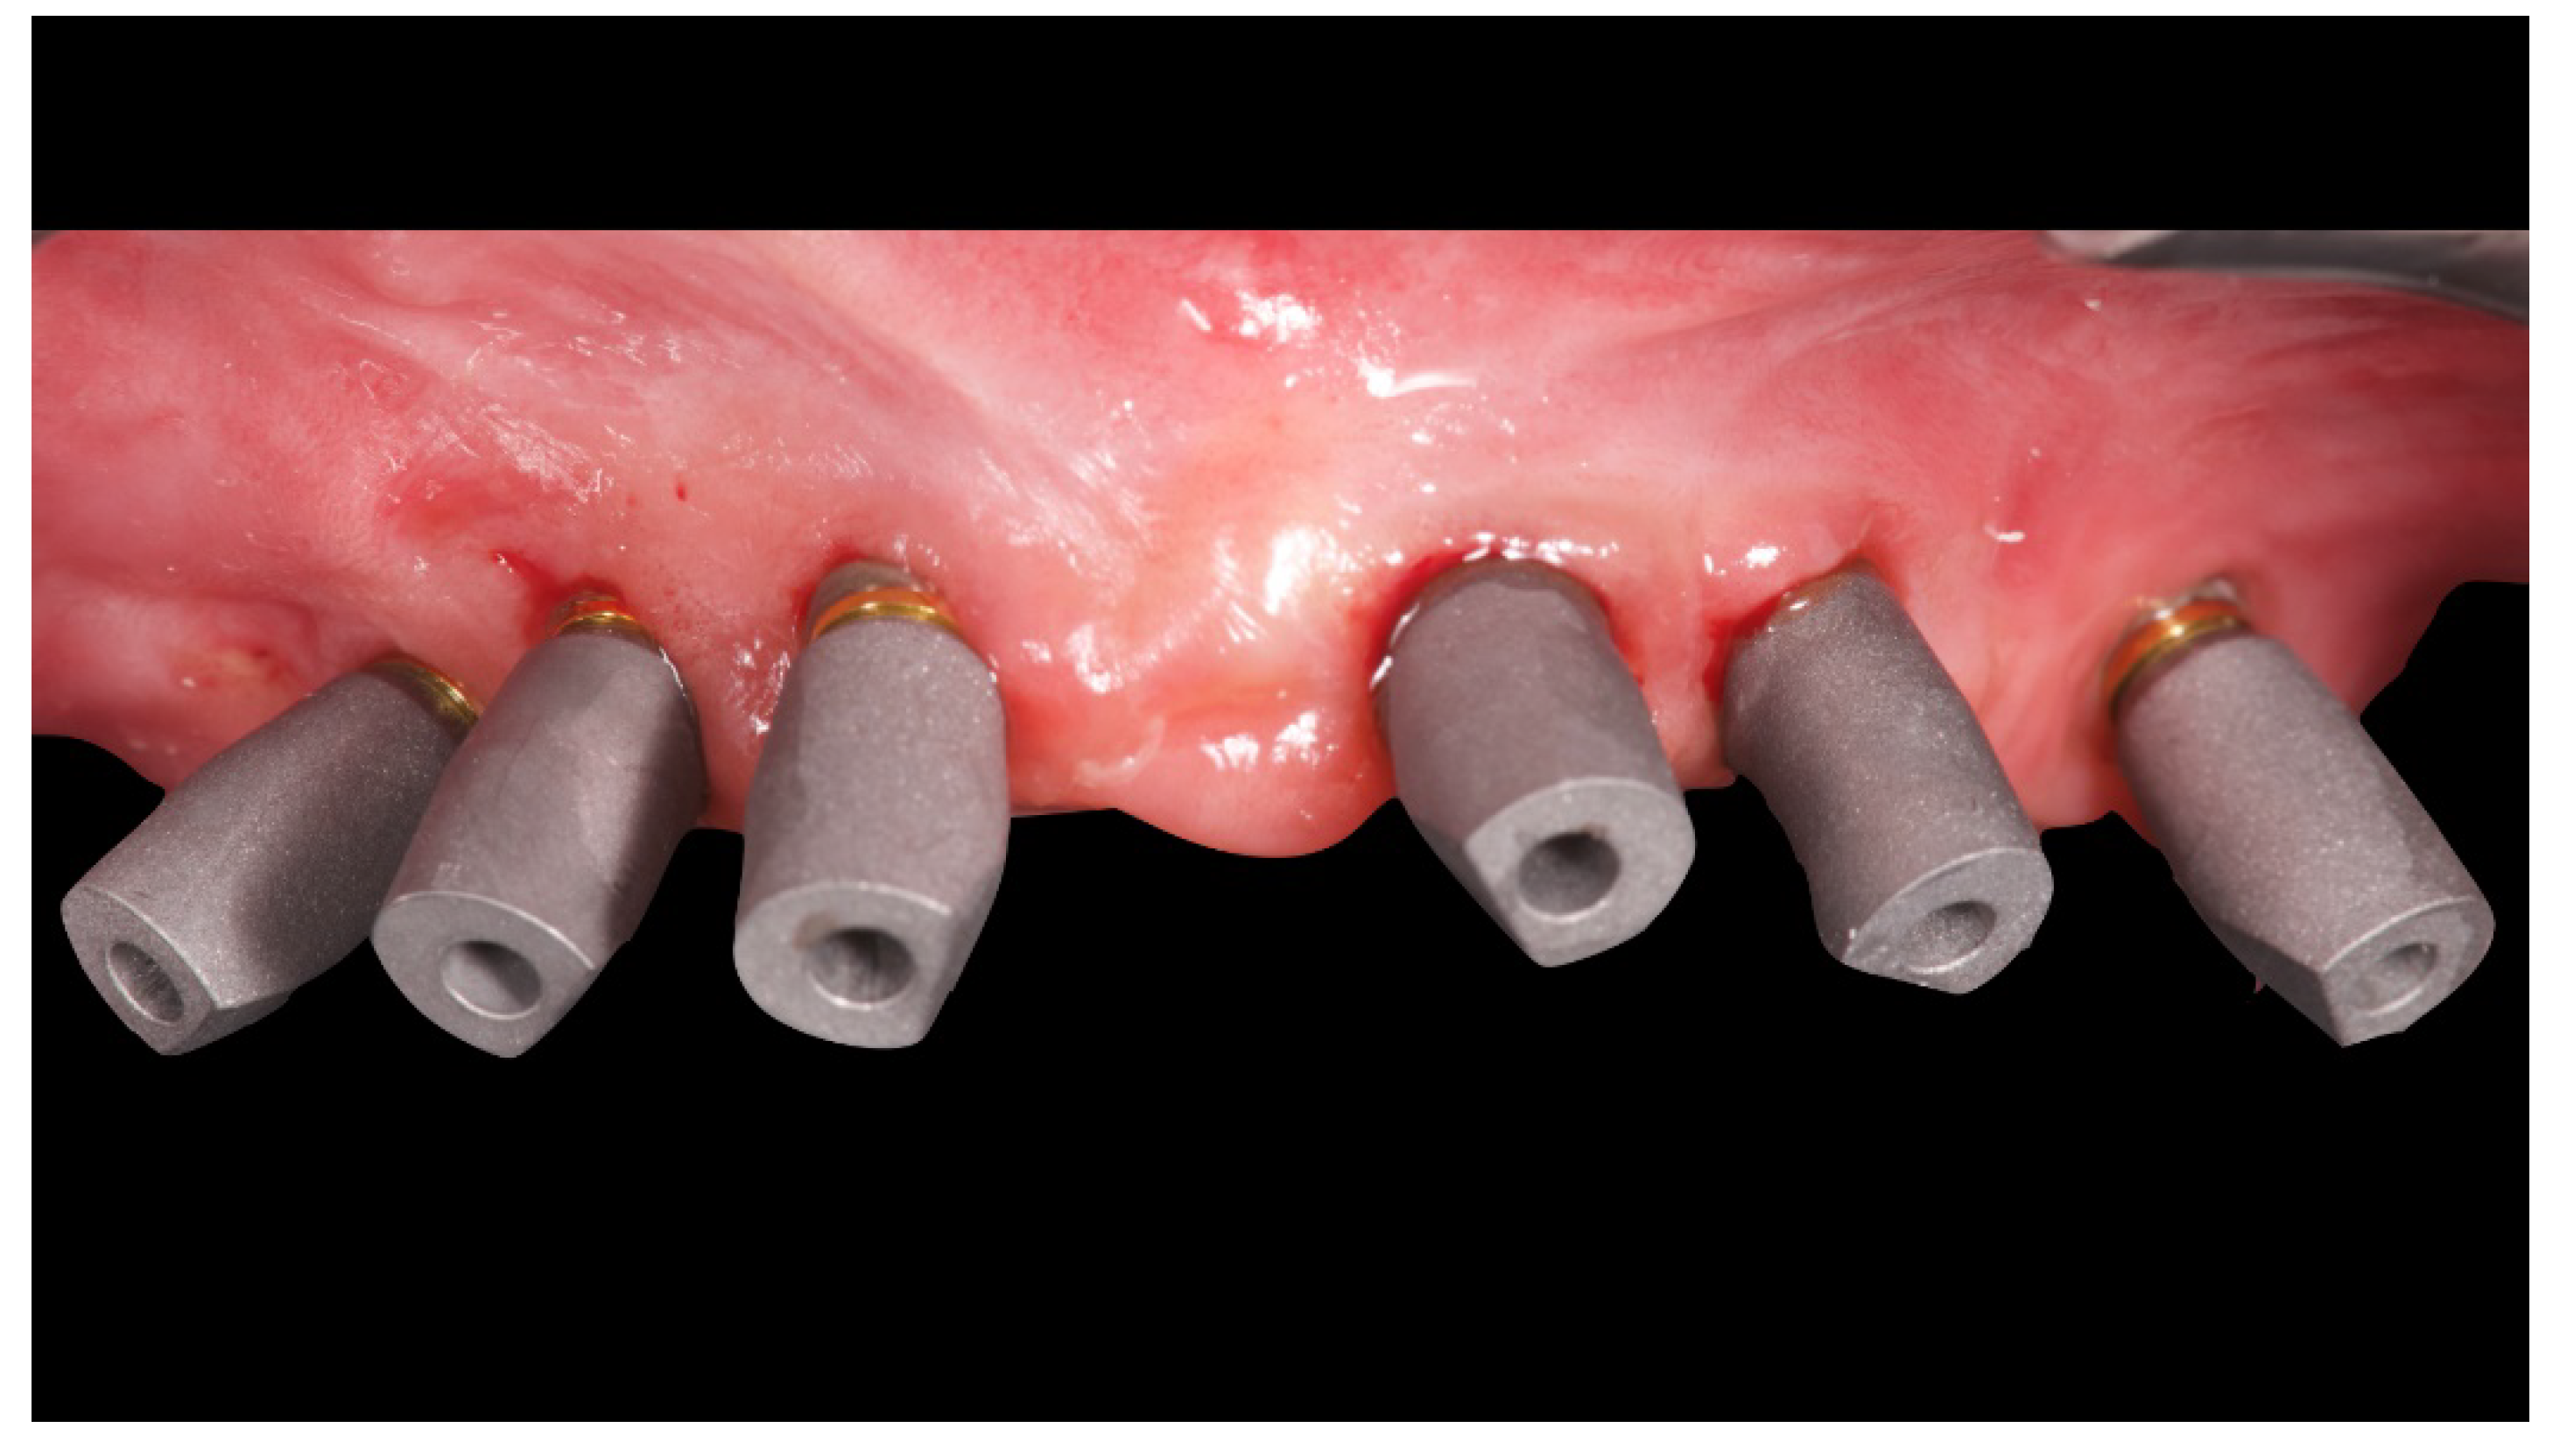

Figure 8.

Analogical transfer screwed on OT Equator for classic impression technique.

Figure 9.

Internal detail of the plaster impression.